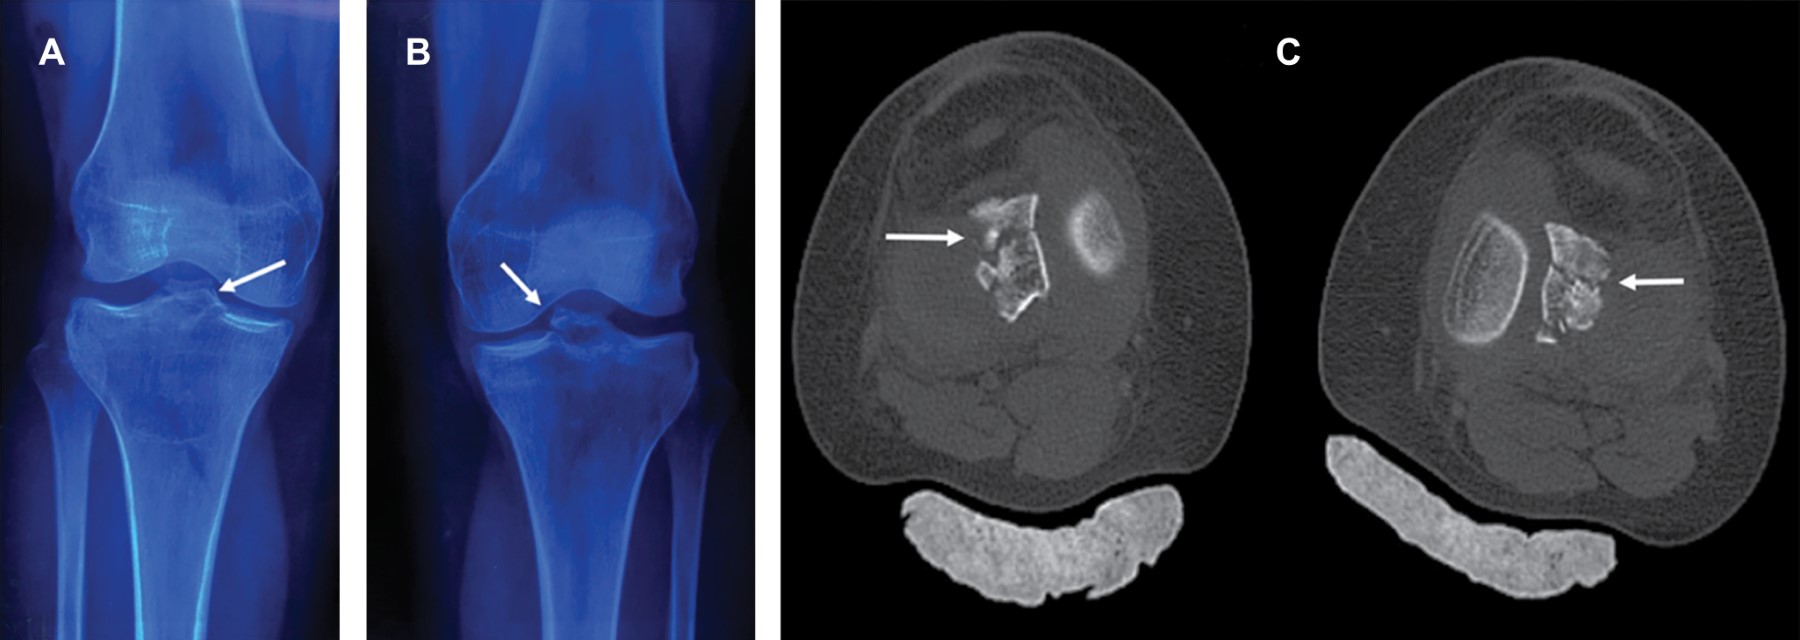

Mujer de 30 años, profesionista, sin antecedentes de importancia, que acude tras caída de 1.5 metros de altura, colisionando ambos talones contra el piso, lo que originó carga axial, hiperextensión y valgo forzado de ambas rodillas, presentando dolor inmediato e imposibilidad para la ambulación. A la exploración gran edema de ambas rodillas por hemartrosis, imposibilidad por dolor para efectuar movimientos de flexoextensión. Resto de exploración normal. Se efectúan radiografías simples de ambas rodillas, encontrando fractura de la espina tibial bilateral (Figura 1A y B), con discreto desplazamiento. Se efectúa tomografía computarizada observando al menos cuatro fragmentos y trazos de fractura (Figura 1C), correspondiendo fractura de espina tibial anterior izquierda Meyers y McKeever tipo IIIB y fractura de espina tibial anterior derecha, Meyers y McKeever tipo II. Se realiza tratamiento quirúrgico mediante artroscopia con guía para ligamento cruzado anterior, reducción y fijación con sutura de alta resistencia tipo FiberWire 2.0 y alambres de Kirschner No. 2.0 (Figura 2) en rodilla izquierda y derecha respectivamente, derivándose a rehabilitación a las tres semanas, se retiraron los alambres de Kirschner a las seis semanas en consultorio; la evolución fue satisfactoria logrando a cuatro meses de rehabilitación: marcha independiente, arcos de movimiento de 130o en ambas rodillas, con fuerza muscular 5/5 en escala de Daniels y pruebas de cajón anterior y Lachman negativas.

Figura 2